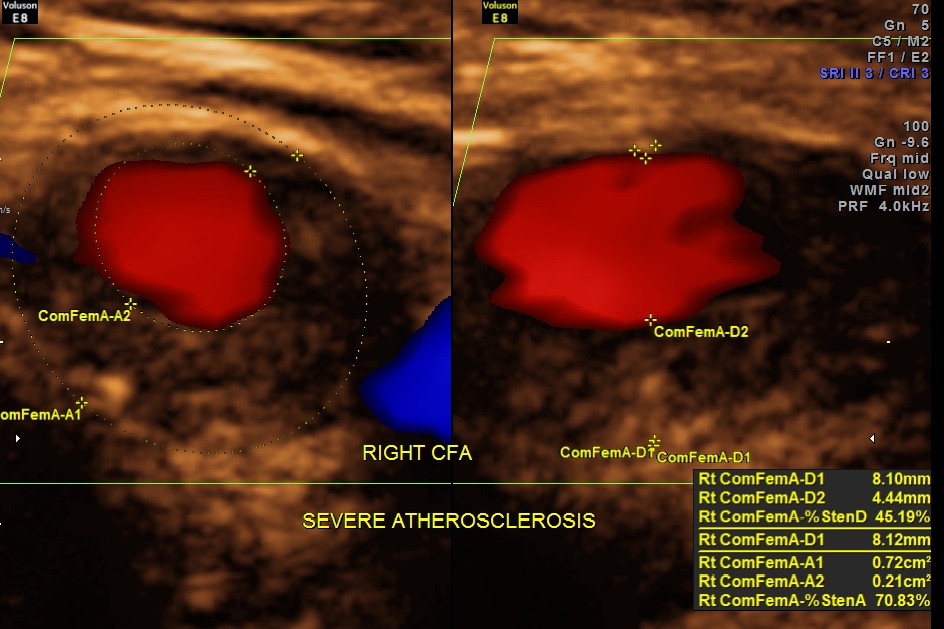

Rt Common Femoral artery showed nearly 70 % obstruction.

EXTENSIVE ATHEROSCLEROTIC OBSTRUCTIVE DISEASE OF THE LOWER LIMB ARTERIES WAS SEEN WITH THE CHANGES IN THE RIGHT COMMON FEMORAL ARTERY BEING MORE THAN THE LEFT CFA.